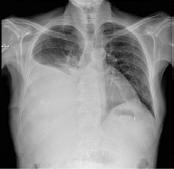

Durante las primeras horas de ingreso, mala evolución clínica y elevación de biomarcadores con procalcitonina 18ng/dL y proteína C reactiva de >350mg/dl por lo que se realiza angio-TC abdominal dónde se observa pancreatitis aguda edematosa con trombosis parcial de la vena esplénica sin otras complicaciones asociadas.

Desde el inicio, predominio de fallo respiratorio hipoxémico refractario a las medidas instauradas con soporte de oxigenoterapia de alto flujo. Controles radiológicos con predominio de colapso pulmonar y atelectasias bibasales. El paciente desarrolla un SDRA grave que requiere intubación orotraqueal en las primeras horas de ingreso y conexión a ventilación mecánica invasiva con problemas de hipoxemia grave e índice PAFI <100 sin mejoría a pesar de intento de optimización respiratoria con relajación neuromuscular y con dificultad para manejo de ventilación en modalidades de pulmón abierto con parámetros protectivos.

Evolución pulmonar radiológica en las primeras 24 h, desde la llegada a Urgencias (A), al ingreso en UCI (B), posterior a la intubación orotraqueal y conexión a ventilación mecánica invasiva (C) y tras la canulación de ECMO VV (D). En la imagen D se observa la punta de la cánula de drenaje femoral (punta de flecha blanca) y la de retorno yugular (punta de flecha negra).

Cortes axial y coronal de TC toracoabdominal en la fase inicial (A y B) y la evolución posterior (C y D). Se puede apreciar la evolución de pancreatitis edematosa (A) a pancreatitis coleccionada (D). A nivel torácico destaca signos de restricción abdominal (B) precoces en probable contexto de hipertensión intraabdominal elevada, con posterior evolución a atelectasia de zonas declives y afectación parenquimatosa heterogénea (D).